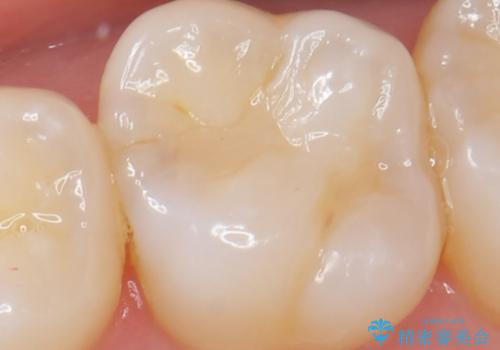

虫歯の発生を初期段階で発見 ゴールドインレー修復

- メンテナンス・検診で数ヶ月に一度定期的に来院されている方の治療例です。

定期的にX線写真を撮影しチェックすることで、外から見てわかるプラークコントロールだけでなく虫歯を初期段階で発見し対策することができます。

歯ぎしりの癖があることから強度に優れるゴールドインレーにて修復を行いました。